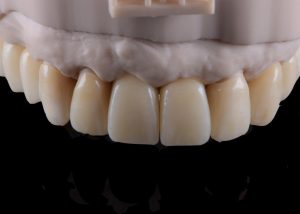

Second set of provisional restorations printed with GC Temp PRINT (medium shade) using the Asiga Max UV 3D printer. Fig. 13

Completed provisional crowns, implant retained crowns and bridge, characterized with OPTIGLAZE color (GC) – Dental technician: Brad Groblar, Oral Dynamics, New Zealand. Fig. 14

Completed provisionals fitted onto the printed models to allow the refinement of the contact points and occlusal contacts. Fig. 15 (i, ii)